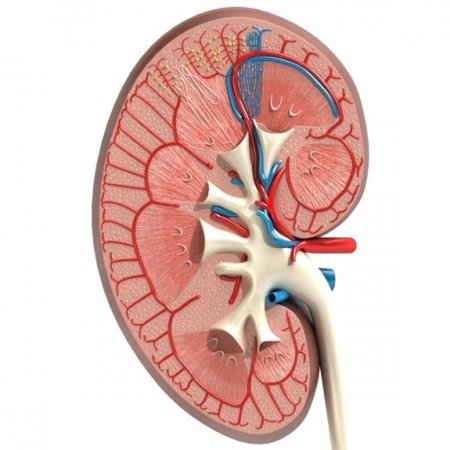

Böbreğin temel fonksiyonlarından birisi idrar üretmektir. Her 2 böbrekte idrar üretimine yol açan yaklaşık 2 milyon küçük ünite (nefron) vardır. Bir nefron temel olarak 2 kısımdan oluşur.

1.Böbreğe gelen kanın süzüldüğü filtre (glomerül)

2.Süzülen kanın idrara dönüştüğü uzun, yer yer kıvrımlı borular (tübül)